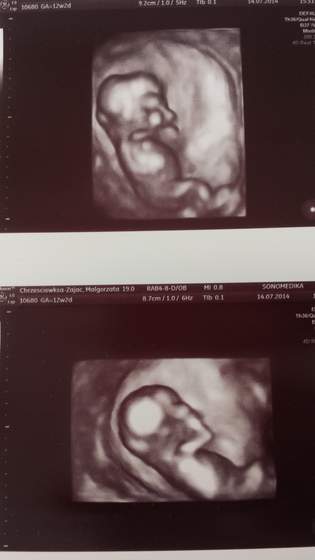

usg prenatalne za nami- w pon a w sr dostalam wyniki papa z krwi.w pon geba mi sie smiala bo z miny pani dr. widac bylo ze zdziwiona ze takie ładne wartosci moja dzidzia jej pokazala ;-)

po przepuklinie pepkowej czy jak tam to sie zwie ani sladu - wszystko ladnie wyglada

a i co ciekawe bylam w 12tyg 2dniu a wg usg 13 + 3 dni (wg wydruku a 13tyg i 4dni(GA) wg tego co na zdjeciu z usg- jakis nonsens bo bo i jak ?!?

dzidzia duza bo 7,42cm wiec jak patrze pod opisy pod waszymi suwaczkami to mam wrazenie ze mam monstrum w brzuchu...(14 tydz i na suwaczku ma 7,5cm) ale chyba co zrodlo to dlugosc ...

a oto moje cudo

plci nie widac bylo

taki rzut z gory co najwyzej ale "ptaszkek" nie wyleciał ;-))) z aparatu...

wygladalo na to ze spi bo byl spokojny tylko jak pani dr włączyła 3d to sie raczkami zasłaniał...